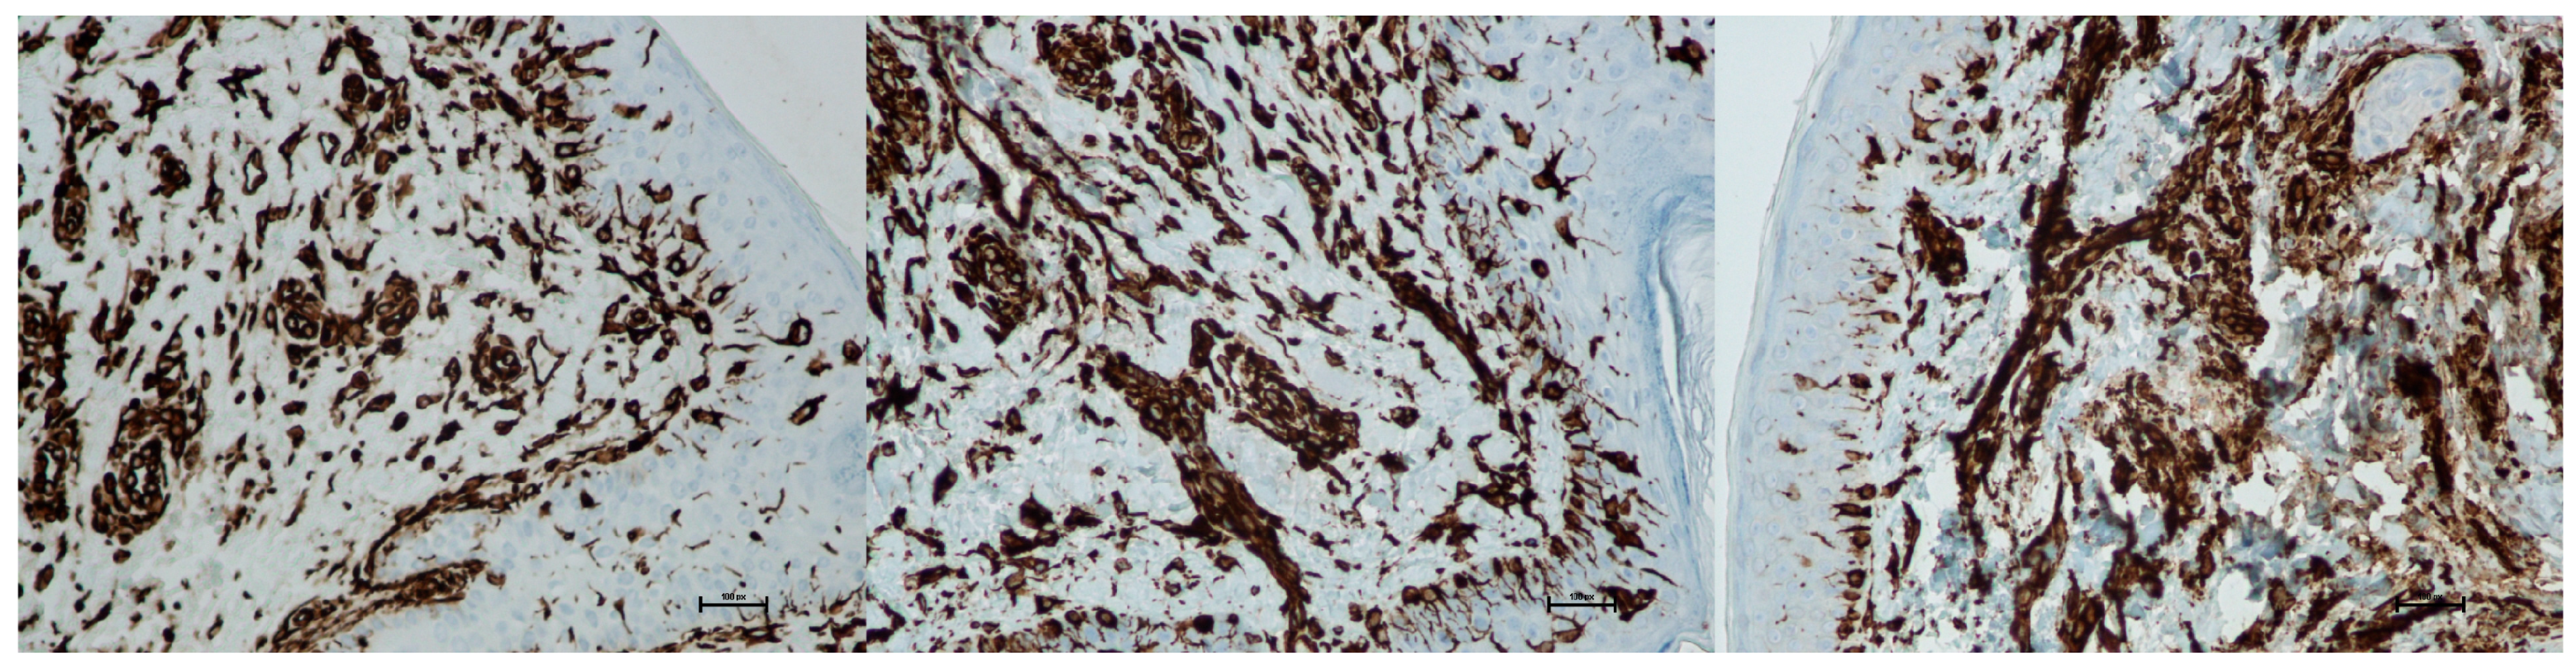

- Histological assessment

- 0: not detected;

- 1: up to 25% infiltration;

- 2: 26–49% infiltration;

- 3: 50–75% infiltration;

- 4: 76–100% infiltration.

- 0: loose, regular fibers;

- 1: loose, irregular fibers;

- 2: dense fibers;

- 3: compact, coarse fibers.

- 0: few, thin-walled vessels;

- 1: increased number of vessels with slight wall thickening;

- 2: increased number of vessels with pronounced wall thickening.

- Results of histological assessment